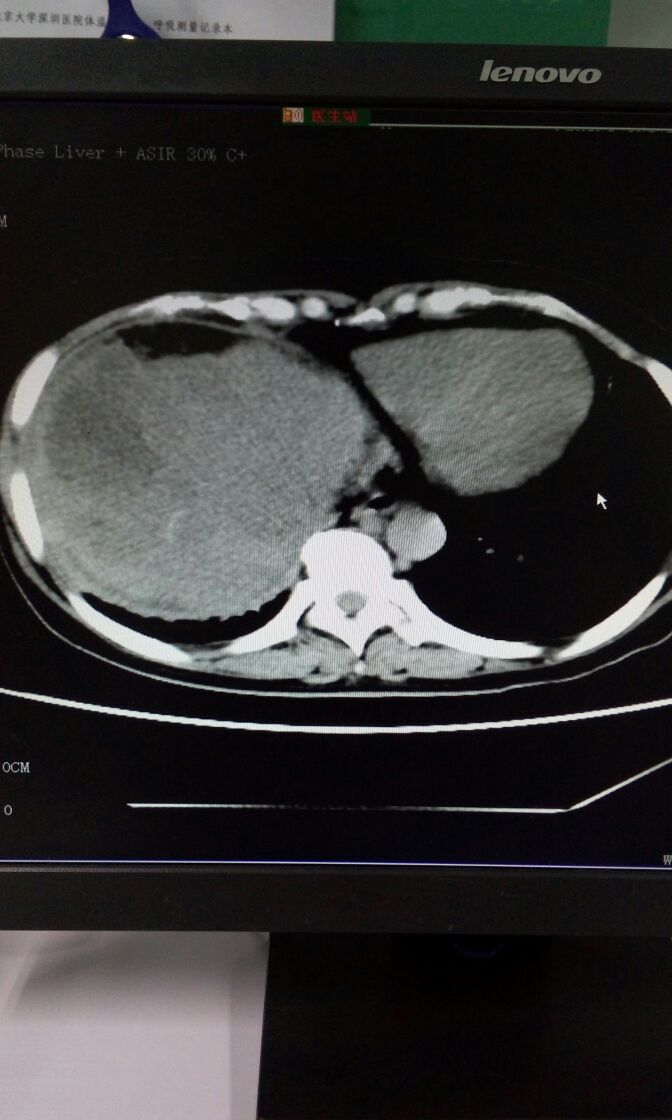

女,56岁,发现丙肝抗体阳性10余年,腹胀10余天。上腹部CT+增强如图。诊断?